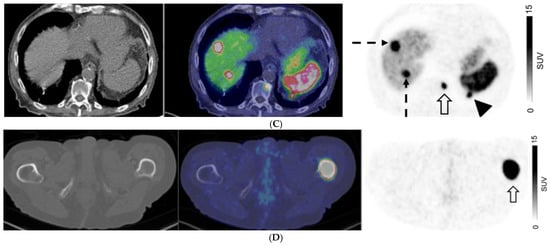

For patients with non-GEP NETs, M0 was confirmed on both CI and PET in 56/104 (53.9%) patients. There were 25/104 (24%) with discordant M-stage on CI and PET. CI and PET suggested liver metastases in 34/104 (32.7%) and 23/104 (22.1%) patients, respectively, and extrahepatic distant metastases in 23/104 (22.1%) and 25/104 (24%) patients, respectively. There were 13/48 patients (27.1%) with non-GEP NETs who had distant metastases on CI but not on PET; 10 of whom had histologically proven distant metastases (Figure 4). When assessing the 47 patients with lung NETs, only 5/47 patients (10.6%) had a higher stage on PET, all of whom had bone metastases with or without liver metastases, while 6/47 (12.8%) had a higher stage assigned on CI, with metastases seen in the liver, lungs, and ovaries.

Figure 4.

A 40-year-old man with metastatic well-differentiated G3 neuroendocrine tumor, unknown primary. Contrast-enhanced CT ((A) Axial image) shows multiple liver deposits (histologically proven; solid arrows) and lytic bone lesion at T12 vertebral body (dotted arrow). 68Ga-DOTATATE PET/CT ((B) Fused axial PET/CT image left and Axial PET image right) show no corresponding focal radiotracer uptake.